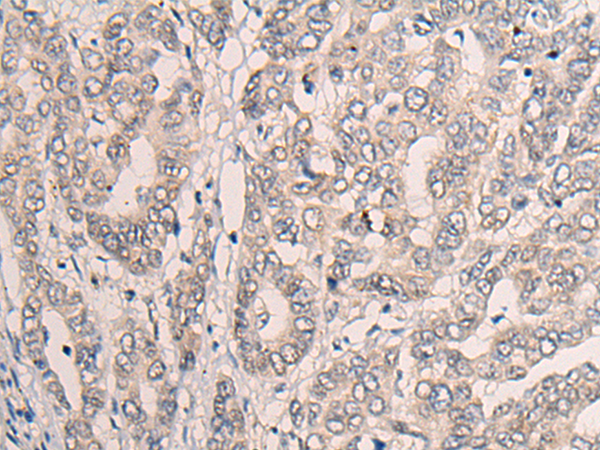

IHC positive control: |

Human liver cancer |